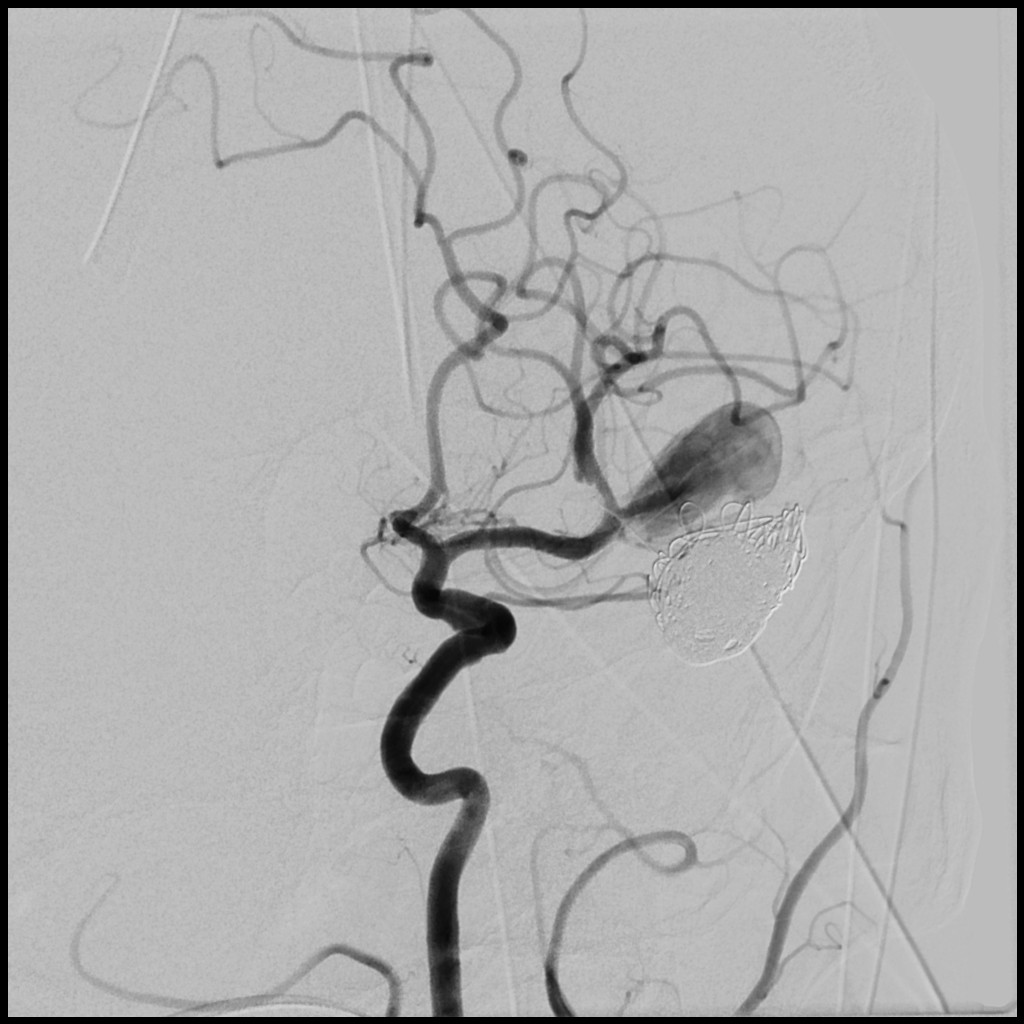

Angiografija: Ova procedura uključuje umetanje kontrastnog sredstva u krvne sudove kako bi se prikazale bilo kakve nepravilnosti tokom snimanja.

Kliping aneurizme: Ova procedura podrazumeva postavljanje metalnog klipa na bazu aneurizme kako bi se sprečilo daljnje proticanje krvi u nju.

Endovaskularna terapija: Ova minimalno invazivna opcija uključuje umetanje katetera kroz krvne sudove radi zatvaranja aneurizme.